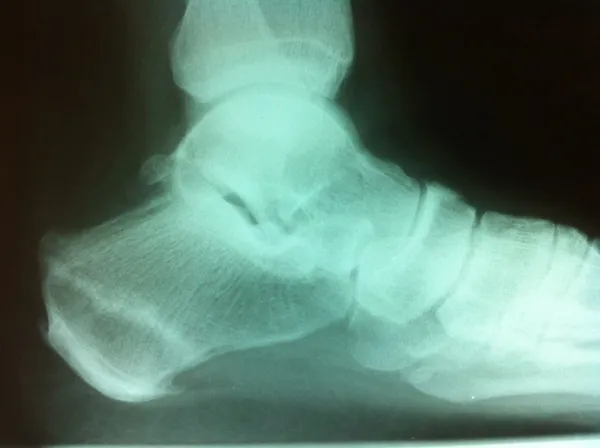

The x-ray image below is a lateral view of the calcaneus (heel bone) in which a fracture line is seen through the bone. This is seen in stress fractures several weeks after the initial injury as the bone begins to thicken as a result of healing of the fracture.

Calcaneal Stress Fracture on Xray and MRI